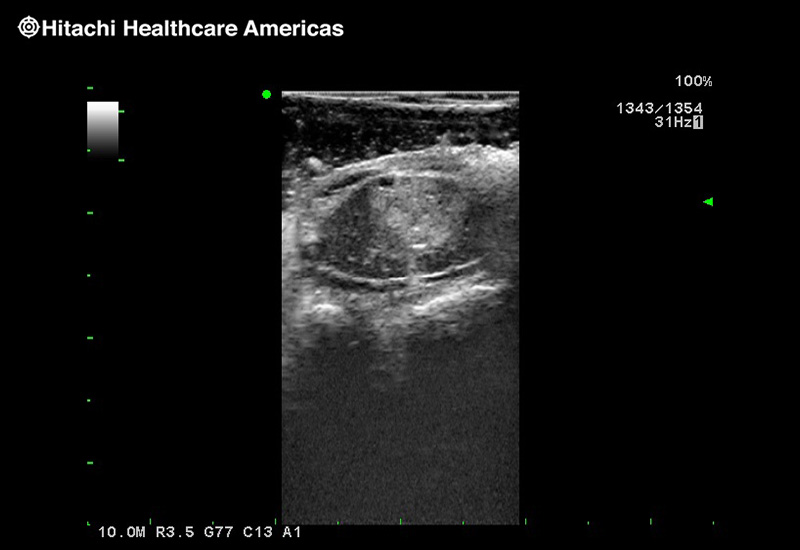

Superior guidance for all applications

Fujifilm Healthcare Americas is committed to designing tools that help surgeons navigate inside the human body and provide the necessary information to immediately make critical surgical decisions.

Fujifilm Healthcare's dedication to Surgeons provides outstanding ultrasound technology, professional support and the specialized tools necessary to best perform comprehensive real-time ultrasound imaging in Breast Surgery, General Surgery, Laparoscopic Surgery, Neurosurgery, Robotic Surgery and Surgical Oncology.

Recognized for our outstanding image quality, outstanding system reliability and intuitive use of cutting edge technology, Fujifilm Healthcare remains the standard in the field of Surgery.

Recognized for our outstanding image quality, outstanding system reliability and intuitive use of cutting edge technology, Fujifilm Healthcare remains the standard in the field of Surgery.